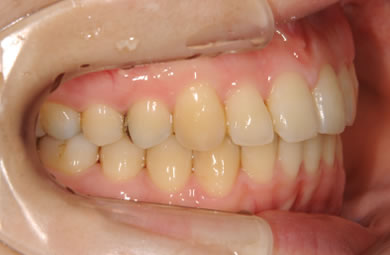

| 性別/年齢 | 女性 / 24歳 | ||||||||||||||||||||||||||||||||

| 治療方針 | 舌が横にはみでて、上下の歯が全く咬んでいない状態です。口元はきれいなので、歯は抜かずに歯列を少し横に広げて並べます。ゴムを使用したり、舌を訓練したりとても協力が必要な症例です。 | ||||||||||||||||||||||||||||||||

| 治療内容 | 唇側矯正(ホワイト)、保定装置 | ||||||||||||||||||||||||||||||||

| 治療期間 | 9ヶ月 |